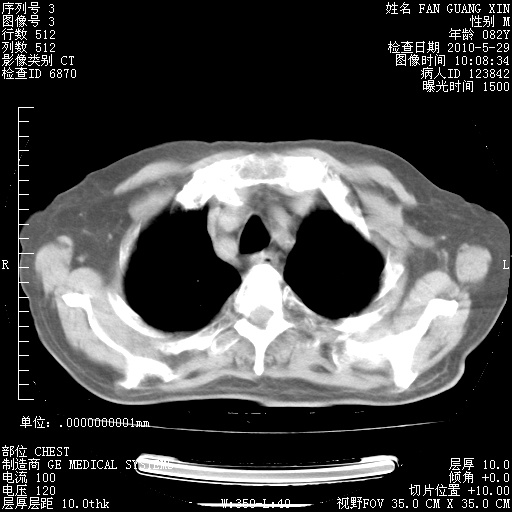

治疗3周后的肺部CT纵隔窗

再治疗10天后的肺部CT